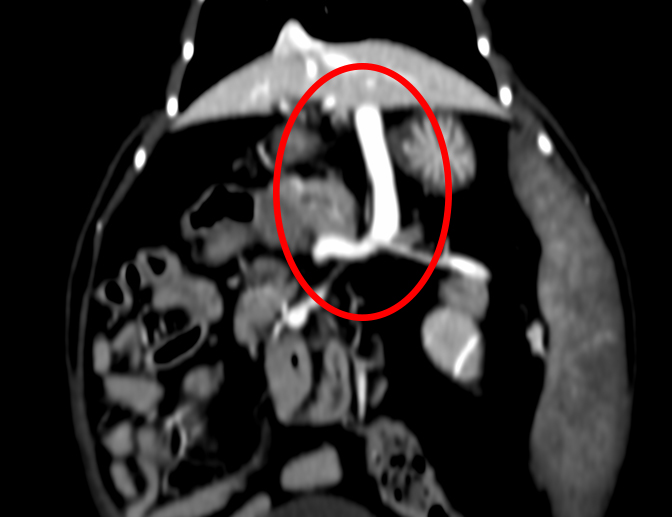

手術前のCT検査での評価(赤丸がシャント血管)